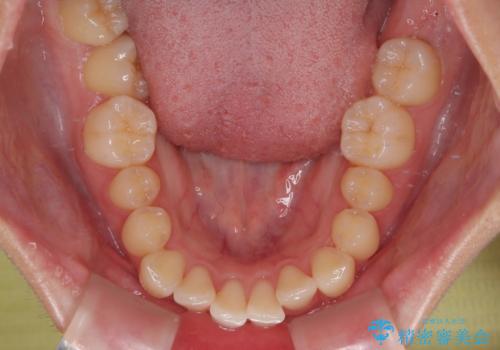

- 上下前歯のデコボコを気にして来院された患者様です。

ワイヤー矯正でもマウスピース矯正でも可能でしたが、短期間で、自身の手を煩わせることなく治療を行いたいとのことで、ワイヤー装置にて矯正治療を行うこととしました。

舌の突出癖により、出っ歯仕上がりとなる可能性がありましたが、舌のトレーニングを頑張っていただき、1年強で終えることができました。